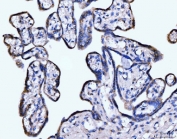

IHC staining of FFPE human placental tissue with Giantin antibody. HIER: boil tissue sections in pH8 EDTA for 20 min and allow to cool before testing.